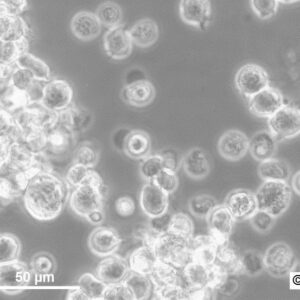

Morphology: Epithelial-like

Growth Properties: Adherent

Description: HuH7 was established in 1982 by Nakabayashi et al. from a 57-year-old Japanese male with well differentiated hepatocellular carcinoma.